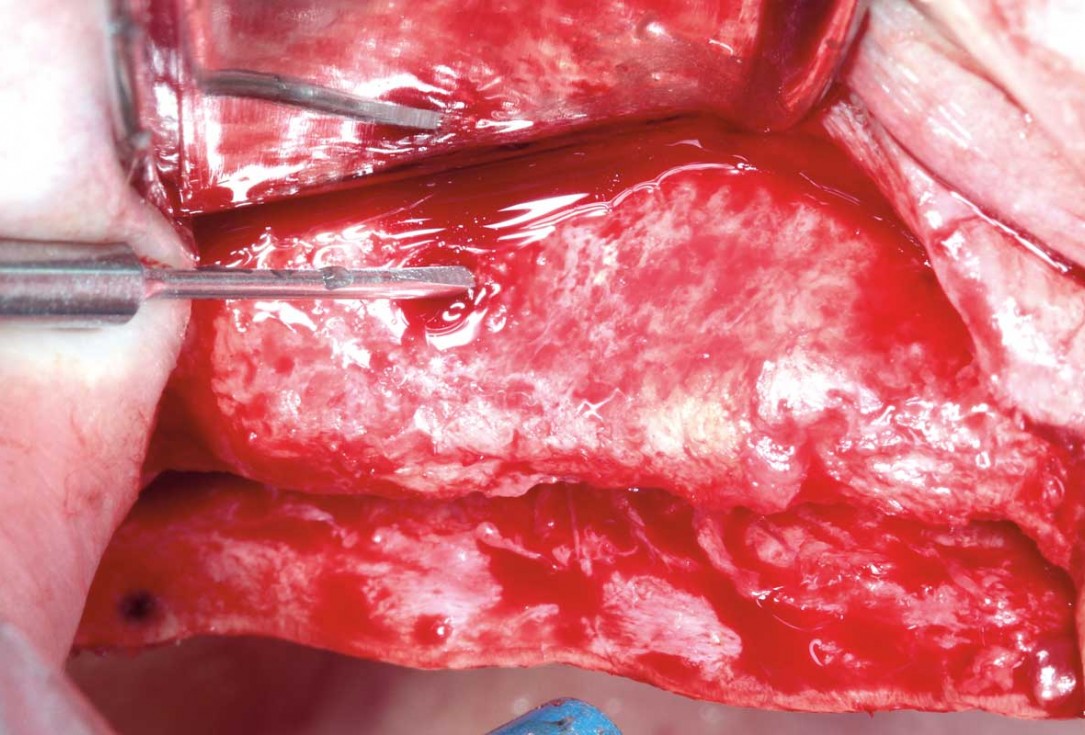

02/12 - Preparation of cortical bleeding pointsHorizontal ridge augmentation with permamem®, cerabone® and autologous bone chips - Dr. S. Pelekanos